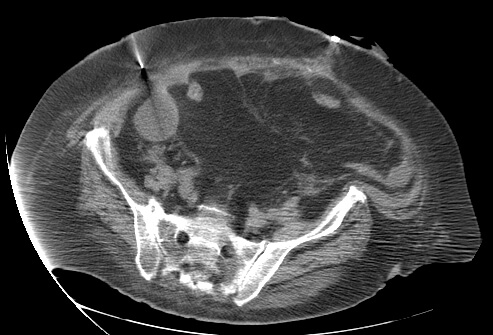

23 year old female with fever and RLQ tenderness s/p appendectomy.

Comment: This case demonstrates performance of a straight-forward CT-guided drainage. Once the abscess was localized on CT and the access site confirmed with a 25g needle, the collection was accessed with a Chiba needle and a guidewire was coiled within the collection. Serial dilatation was then performed so that a pigtail drainage catheter could be placed within the collection for drainage.